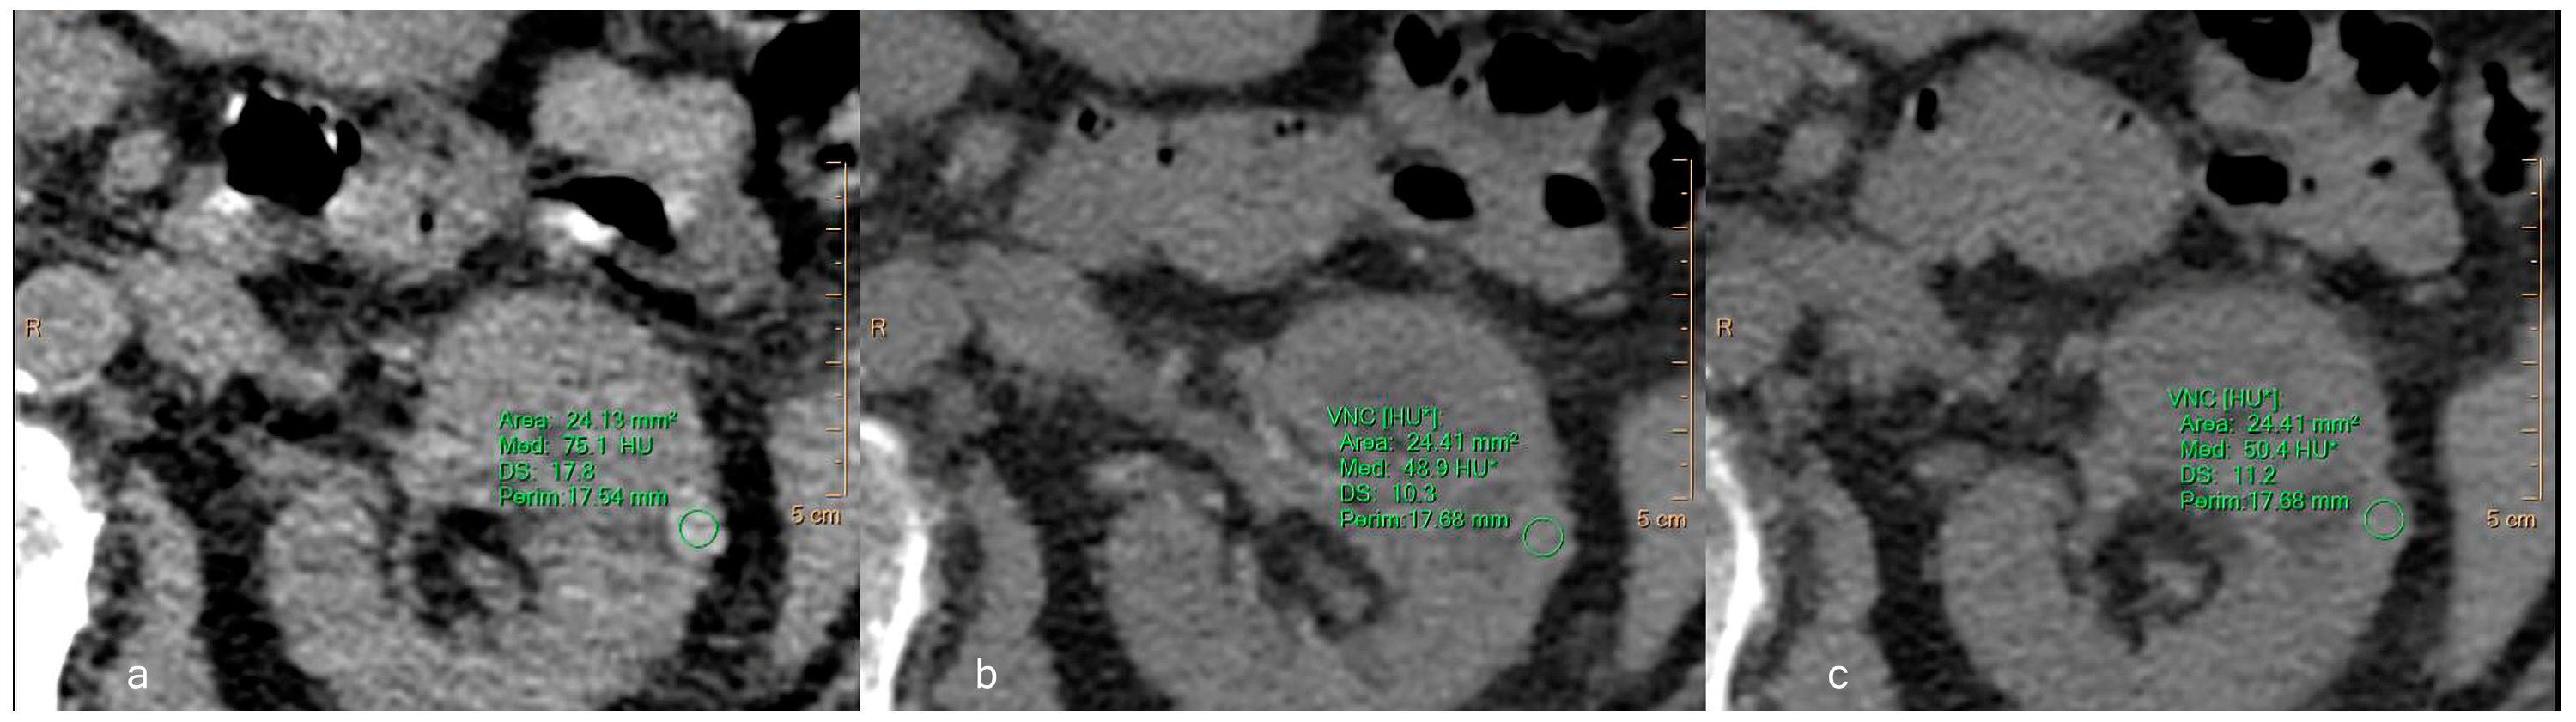

Virtual Non-Contrast Spectral CT in Renal Masses: Is It Time to Discard Conventional Unenhanced Phase?

3. Results

3.2. Quantitative Assessment